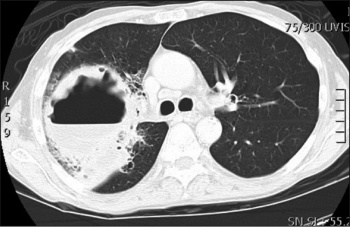

Figure 1. Chest x-ray showing a large cavitating lesion in the right upper lobe

Figure 1. Chest x-ray showing a large cavitating lesion in the right upper lobe(click to enlarge)

The bedside urinalysis was clear and the ECG was showing a sinus rhythm. His blood tests were predominantly unremarkable with the exception of a C reactive protein of 117 (<10mg/l) and mildly deranged liver function tests. The total white cell count (WCC) was 9 (4-10x109/l). Quantiferon, ACE, ANCA were negative. The chest x-ray showed what appeared to be a large cavitating lesion in the right upper lobe with an air/fluid level (see Figure 1).